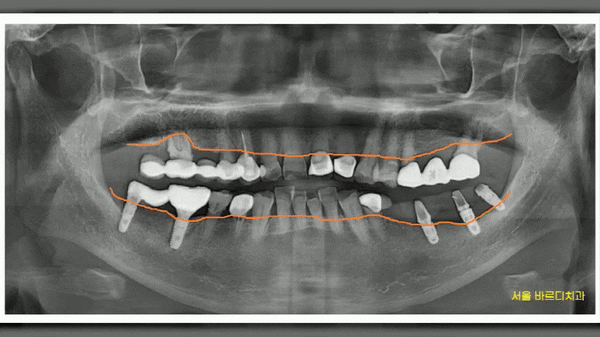

위아래 양쪽으로 치료를 하신 환자분

잇몸뼈가 전반적으로 많이 녹기도 하였고

오래 전 한 보철이 문제가 있엇습니다.